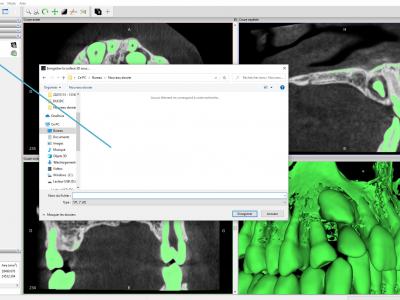

- Exporter la surface 3D au format STL

2. Nettoyer le fichier STL

Avec le logiciel gratuit Meshmixer

- Importer le fichier STL